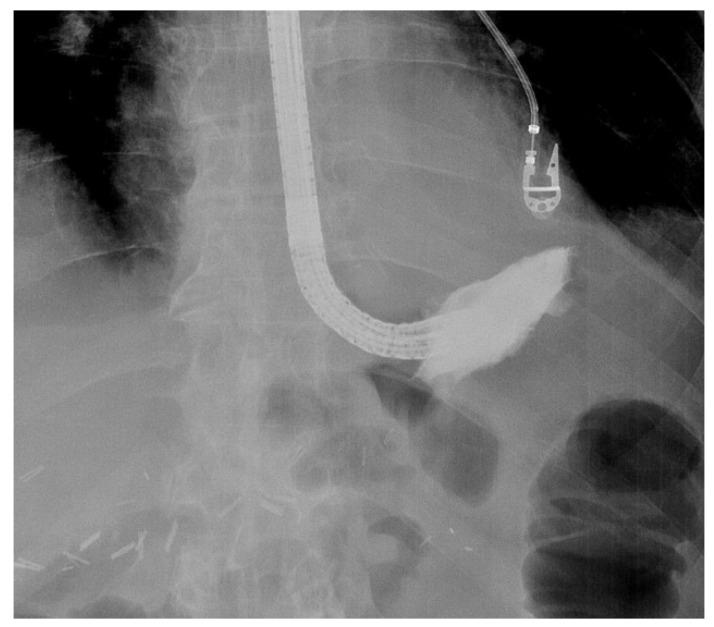

Anastomotic leaks after gastrointestinal surgery have an important impact on surgical outcomes because of the high morbidity and mortality rates. Multiple treatment options exist requiring an individualized patient-tailored treatment plan after multidisciplinary discussion. Endoscopic vacuum therapy (EVT) is a novel treatment option that is nowadays recognized as an effective and useful endoscopic approach to treat leaks or perforations in both the upper and lower gastrointestinal tract. EVT has a very good safety profile. However, it is a time-consuming endeavour requiring engagement from the endoscopist and understanding from the patient. To the unexperienced, the EVT technique may be prone to several hurdles which may deter endoscopists from using it and depriving patients from a potentially life-saving therapeutic option. The current review highlights the possible difficulties of the EVT procedure and aims to provide some practical solutions to facilitate its use in daily clinical practice. Personal tips and tricks are shared to overcome the pre-, intra- and post-procedural hurdles. An instructive video of the procedure helps to illustrate the technique of EVT.

胃肠手术后的吻合口漏由于其高发病率和死亡率,对外科手术结果有重要影响。存在多种治疗选择,需要在多学科讨论后制定个体化的患者定制治疗方案。内镜下真空治疗(EVT)是一种新型治疗选择,如今被认为是治疗上、下消化道漏或穿孔的一种有效且有用的内镜方法。EVT具有非常好的安全性。然而,这是一项耗时的工作,需要内镜医师的参与以及患者的理解。对于没有经验的人来说,EVT技术可能容易遇到几个障碍,这可能会阻碍内镜医师使用它,使患者失去一种可能挽救生命的治疗选择。本综述强调了EVT操作可能存在的困难,旨在提供一些实用的解决方案,以促进其在日常临床实践中的应用。分享了个人的技巧和窍门,以克服术前、术中和术后的障碍。一段该操作的指导性视频有助于说明EVT技术。